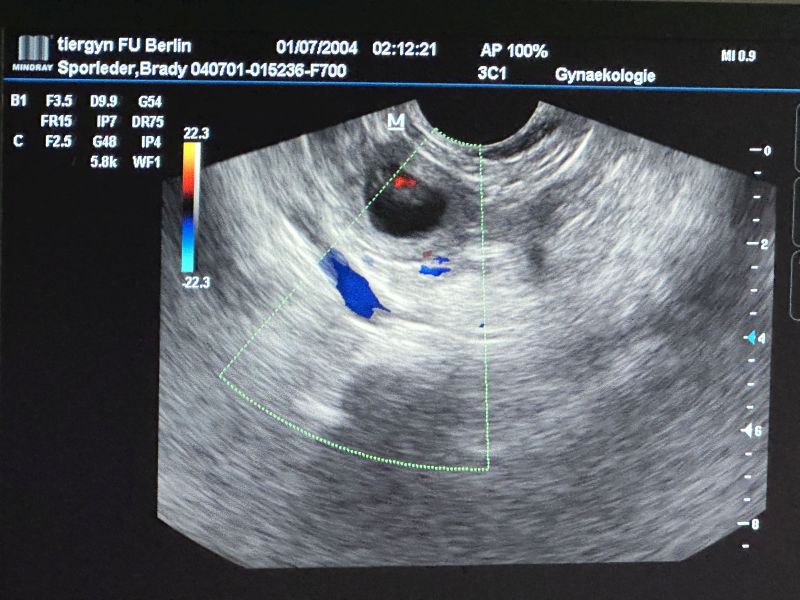

Das Ultraschall hat Gewissheit ergeben.

Weiterlesen: Braydee ist tragend